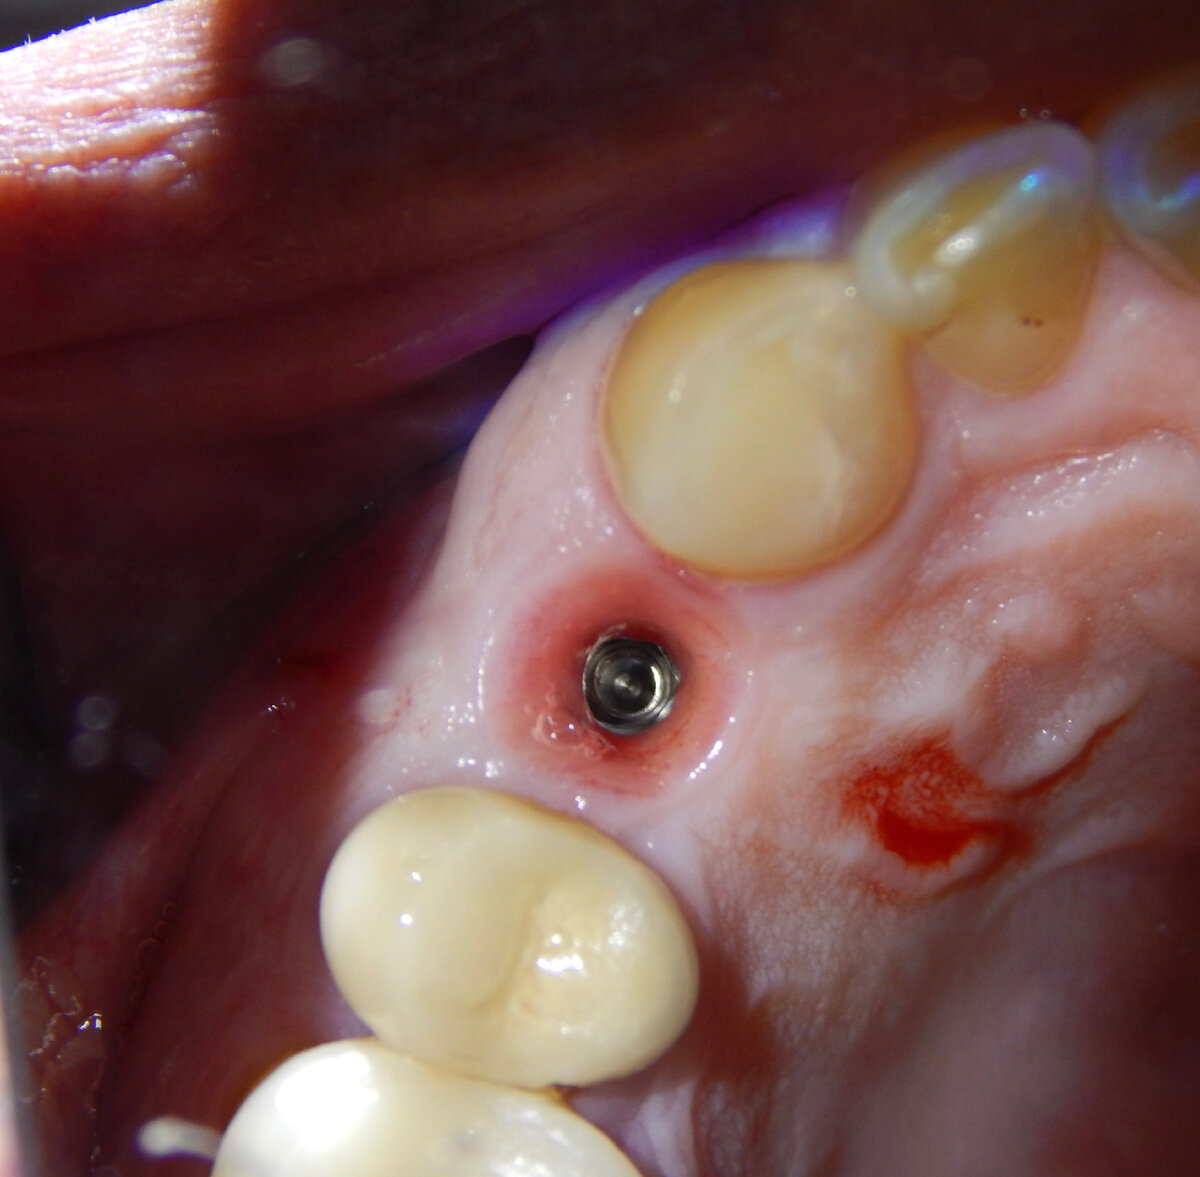

Фото после снятия постоянной коронки

Визуально кажется, что проблемы никакой нет. Всё заживает после операции хорошо. По истечению 2,5-3 месяцев на контрольном осмотре слизистая вокруг совершенно здорового бледно-розового цвета. При дотрагивании вокруг тоже всё, как в Багдаде, спокойно. Формирователь десны стабилен, на месте, перкуссия постукивания по нему не вызывают никаких болевых и дискомфортных ощущений у пациента. И все участники процесса думают, что всё 👌.

И только когда наступает период ортопедического лечения (обычно через 2.5-3 мес.) можно выявить этот странный феномен. К счастью он встречается довольно редко, но к сожалению это иногда происходит. На моей памяти за 11 лет это второй случай.

Ортопед ко мне подходит и говорит о странных моментах возникших при фиксации коронки на имплантат:«Что-то не то происходит, не как обычно всё».

«Зафиксировал коронку, но ощущение, как будто что-то провернулось при фиксации. Назначил пациента ещё раз через 3 дня к себе и попробовал повторно затянуть фиксирующий винт. При этой манипуляции пациент почувствовал дискомфорт. Сделал прицельный снимок. И решил назначить его совместно на осмотр».